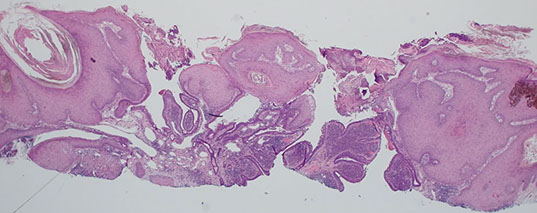

Spiradenoma

Usually presents as solitary, violaceous, gray-blue nodule that tends to arise on the ventral aspect of the head, neck, trunk, and sometimes extremities

- usually young adults (15-35 yo), can be painful

May be found in Brooke-Spiegler syndrome (cylindromas, spiradenomas, trichoepitheliomas)

Closely related to cylindroma (may occur as a hybrid tumor), those these are usually sporadic whereas cylindromas are multiple and inherited

- spiradenomas may present as a tender nodule

Micro: Large ball of dark blue cells (cannonballs) that are not attached to the epidermis tc interspersed black lymphs and paler cells in the middle of the ball c dark red droplets of hyaline

DDx: considered sometimes to be on a spectrum with cylindroma